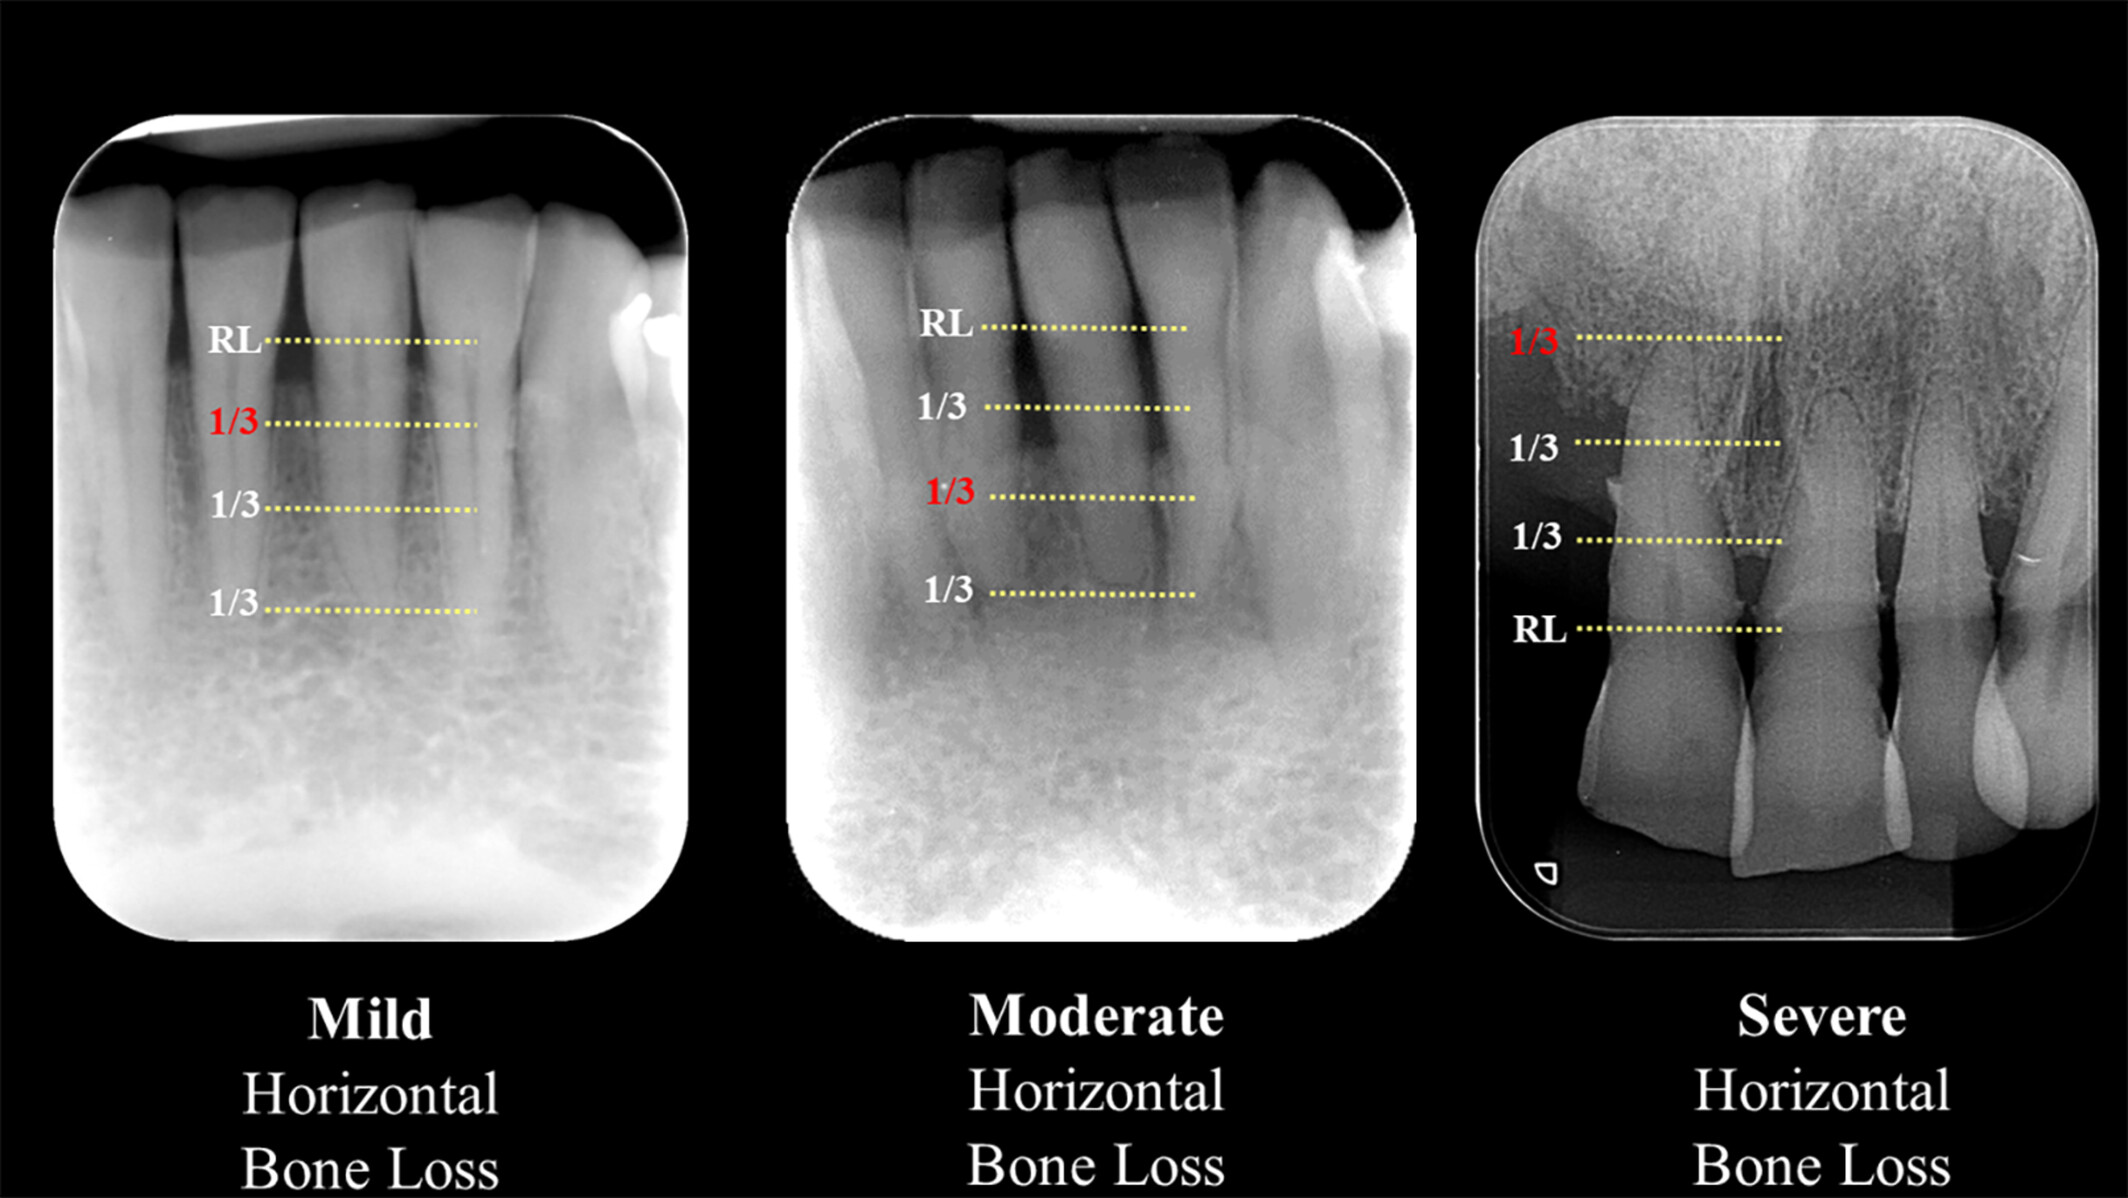

Figure 1. Sévérité de la perte osseuse horizontale (léger, modéré, sévère)

Trois radiographies rétroalvéolaires des incisives mandibulaires illustrant la perte osseuse horizontale : léger (perte limitée au tiers coronaire de la racine), modéré (tiers moyen) et sévère (tiers apical). Les pointillés jaunes et la ligne de référence (RL) divisent la longueur radiculaire en tiers ; le tiers concerné est souligné en rouge. Critères radiographiques utiles pour évaluer la gravité de la parodontite.